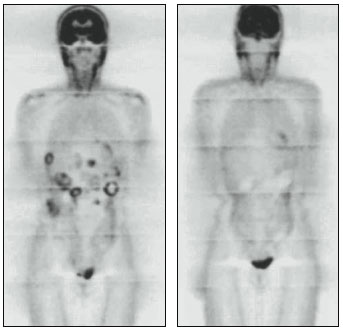

Two weeks later, an MRI exam showed the woman's tumors were 40 percent smaller. Two months later, they had shrunk half as much again. At eight months, they were further reduced in size; about a quarter were no longer detectable. What's more, the tumor cells that remained had stopped dividing and no longer showed the molecular signature of cancer. It was an incredible improvement.

Images courtesy of Heikki Joensuu

To grasp the striking success of imatinib, one needs to understand that prior to its use there were no good treatments for GISTs. Most of these tumors are highly resistant to chemo- and radio-therapy, and multiple surgeries were the only palliative option. Now, the combination of surgery and imatinib benefits more than 80 percent of patients. Unfortunately, this upswing is only a respite in some cases. The tumors vary in their genetic make-up, which presumably explains the slow remedy seen by some patients and the unresponsiveness of others. The latter group often carries tumors that have little or no KIT protein, a variety that can also be found among patients who initially respond well to the drug, but worsen as the susceptible cells die off, leaving others to spawn new tumors that resist imatinib.